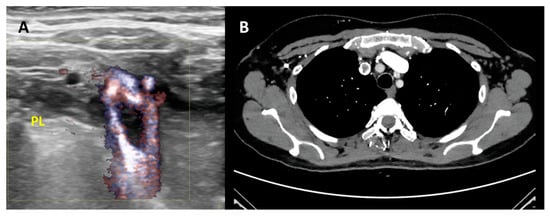

CT Venography can provide a rapid and reliable modality for detecting IJVthr (Figure 3). CTV is much more useful in subacute or chronic situations because of the varied density in thrombosed sinus.

Figure 3.

Second level diagnosis of IJVthr. (A) Case of right IJVthr with a floating thrombus approaching the superior vena cava; high resolution ultrasound complemented by B-flow enhances the black floating thrombus. PL = pleural line. (B) Same case demonstrated by angio-TC.